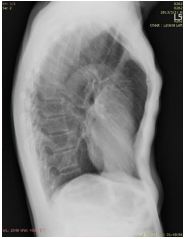

2. A 27-year-old woman had productive cough for one month.